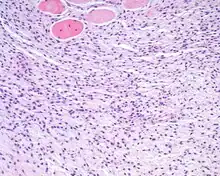

An intermediate power hematoxylin and eosin stained section of an ectomesenchymal chondromyxoid tumor, showing skeletal muscle entrapment. Note the "net-like" appearance (lower portion).

The cells may extend into and entrap soft tissue structures including skeletal muscle and nerve bundles.

The overlying surface epithelium is intact and unconnected to the well circumscribed, but unencapsulated ectomesenchymal chondromyxoid tumor of the tongue. There are numerous skeletal muscle bundles at the periphery of the tumor.